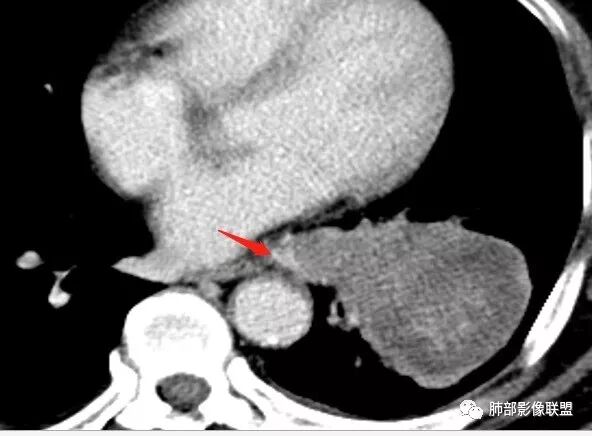

恶性没问题吧  ,哪位老师标示一下病灶

那些是淋巴结?哪是主病灶?

支气管如何?肺动脉?肺静脉?

南边:我发一个图

南边:这病灶与支气管啥关系啊?

南边:与肺静脉啥关系?这样追下去是不是很恶啊

尘缘:@南边 肺静脉受侵

南边:病灶分为两大块,外围囊实性大肿块,支气管关系不密切,内带多发淋巴结,侵犯支气管、肺血管,恶性没问题,按理间叶为主,或不典型的癌,这不是一个中央型的肺癌,是外朝内进展的,奇怪的是边界这么清楚光滑,一般癌肉瘤、肉瘤类多,其次才是癌,远端也没有阻塞,大方向是这样,恶性,间叶来源?或者混合,恶性程度较高,鉴别就是结核,因为结核是妖

1.左肺下叶近肺门区肿块,肿块外围大,内带小,提示外围向中央生长,符合周围型SCLC沿支气管方向生长。

4.病灶区支气管以受压推移为主,管腔不规则,腔内通而不畅,提示病灶粘膜下为主,符合SCLC迁徙蔓延或间叶来源肿瘤。

5.病灶内有血管走行,血管局部受压,但是强化考虑为乏血供,提示病灶内肺动脉并不是供血血管,只是病灶侵袭性强把血管包埋而已,为血管包埋征;血流面光滑,血管包埋符合SCLC。

6.左肺门淋巴结肿大,与病灶局部融合分界不清,呈冰冻肺门;而纵隔内未见肿大淋巴结,冰冻肺门符合SCLC,但是病灶主体那么大,纵隔内没有明显肿大淋巴结,不是很符合SCLC娘小崽大的特点。